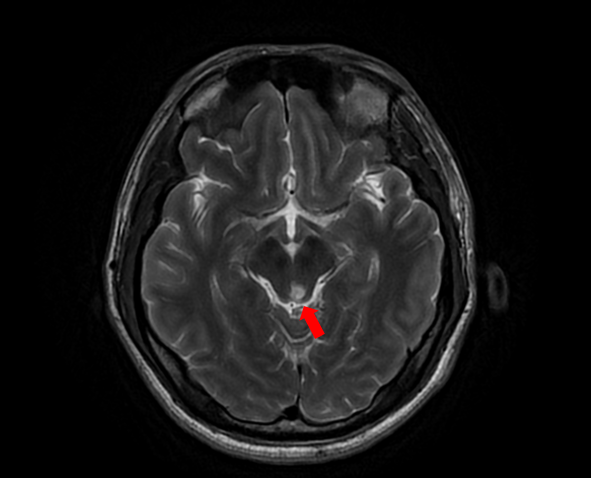

随着患者高先生颅内中脑左侧、左侧小脑两处病灶的顺利切除,国际神经外科医生集团专家已累计在苏大附四院完成了第100例高难手术。这标志着我院在神经外科国际化合作交流方面取得了里程碑式的成果,也为众多疑难脑肿瘤患者带来了新的希望。